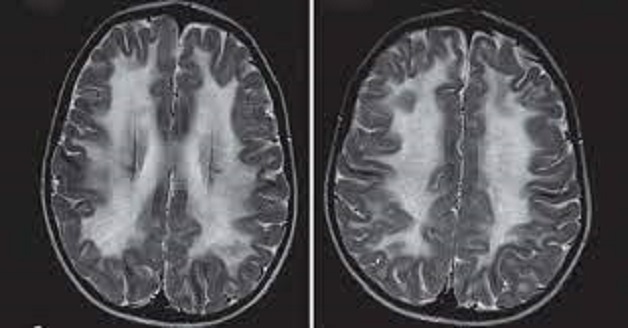

Thoái hóa chất trắng là một trong những nguyên nhân gây suy giảm trí nhớ, mất ngủ ở người cao tuổi.